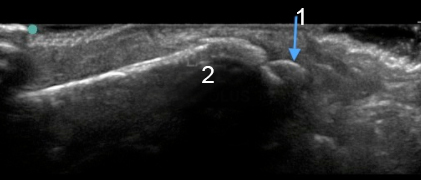

Lateral Malleolus Avulsion

Lateral Malleolus